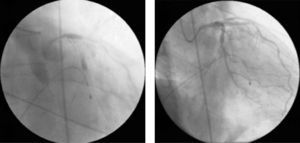

Cardiac catheterization was performed the following day, which revealed focal type A lesions in the proximal left anterior descending artery (LAD) and mid circumflex artery (Fig. 1).

Ad-hoc angioplasty was performed on both vessels with direct stenting (Fig. 2), using standard intracoronary devices (3.0mm×12mm in the proximal LAD and 3.0mm×15mm in the circumflex artery).